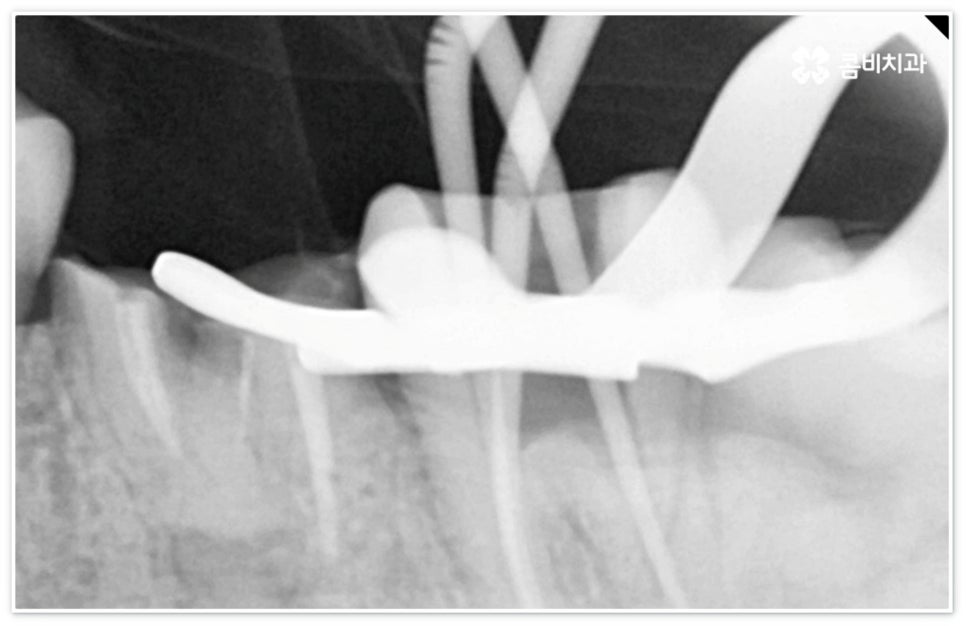

신경치료는 일견 간단해 보일 수 있으나 사람의 신경이 매우 얇고 또한 환자분들마다 신경관의 개수와 모양이 다 다르기 때문에 오염된 부위를 끝까지 깨끗하게 제거하기 위해서는 매우 섬세하고 뛰어난 기술력을 요하므로 다양한 임상 경험을 통해 풍부한 노하우를 가지고 있는 의료진과 함께 하실 필요가 있습니다.

신경치료는 오염된 치수 조직을 제거하여 감염이 더이상 진행되지 않도록 하고 치과용 충전재로 내부를 빈틈없이 채운 후 크라운 보철물을 씌워 남아있는 자연 치아를 쓸 수 있도록 하는 치료이기 때문에 그 과정에서 치아 깊숙한 곳까지 기구로 파고들어 가므로 주변 치아 조직이 예민해지면서 치료 후 며칠에서 길게는 몇 주까지 신경치료통증 을 느끼실 수 있는데요.

혹여 미세한 부근관의 염증을 놓치거나 사후 외부 원인으로 2차 감염이 일어나는 경우 신경치료통증 이 오래 지속될 수 있으니 며칠이 지났음에도 욱신거림이 줄어들기는 커녕 점차 심해진다는 느낌이 있다면 다시 한 번 치과로 내원하셔서 꼼꼼하게 검진 후 필요한 치료를 받으시는 게 좋을 거예요. 상황에 따라 재신경치료를 진행해야 할 수도 있고 좀 더 지켜보면서 발치가 불가피하지는 않은지 신중하게 판단해야 할 수도 있는데요. 예를 들어 만약 신경치료통증 의 원인이 치료 전부터 치아 뿌리에 생겼던 미세한 균열 때문이라면 치료 받은 치아로 씹을 때 통증이 지속적으로 나타날 수 있고 재신경치료 등으로 이를 살릴 수 없으므로 이 통증이 일상생활에 큰 영향을 주지 않을 경우 최대한 사용하는 데까지 사용을 하다가 임플란트 치료를 권장 드리고 있으나 증상이 심할 경우 바로 발치를 해야 하며, 매우 낮은 확률이긴 하지만 신경관 내부 뿐 아니라 외부에도 세균 군집이 생겨 치아 뿌리 끝 염증이 나아지다가 다시 악화된 상황이라면 역시 약 처방 등으로 신경치료통증 을 잡을 수 없고 발치 후 임플란트 식립을 통해 치료해야 할 거예요.